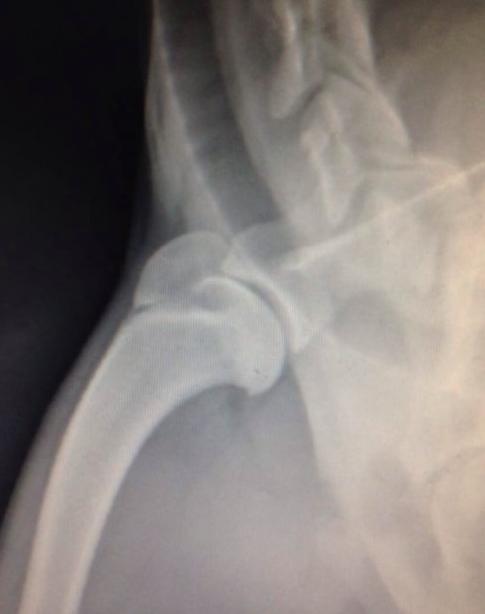

11个月小狗肩关节骨软骨病

为了达到准确的评估结果,兽医会请放射科医生为小狗每个患病的部位进行X光片,可清楚了解到疾病的严重程度,而X光片是诊断这类疾病的最常用方式。